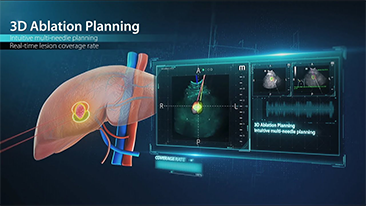

Mindray Resona Genel G?rĂŒntĂŒleme ??zĂŒmleri, kapsaml? alt b?lĂŒm uygulama problar? ve verimli klinik uygulama ara?lar? arac?l???yla, klinisyenlerin daha do?ru ve verimli tan? ve tedavi sonu?lar? elde etmesine yard?mc? olur.